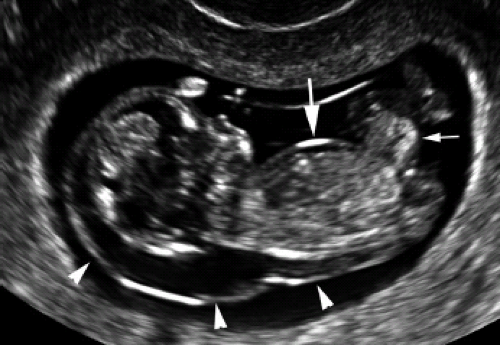

11-14 hafta testi sırasında ultrasonografinin önemli bir yeri var. Bu testtki en önemli veri bebeğin ense pilisinin ölçümüdür. Down sendromlu veya başka bir çok genetik hastalıkta olduğu gibi bazı kalp hastalıkları, akciğer hastalıkları, iskelet hastalıklarında bebeğin ense kısmındaki sıvı birikimi artar. Bu bölgenin ölçümü milimetrenin onda biri ölçeğinde gerçekleşmekte olup sanılanın aksine zor ve hassas bir işlemdir. Doğru ölçümü yapabilmek için bazen hekim oldukça uzun bir zaman ayırmak zorunda kalabilir. Bebeğin o andaki pozisyonu etrafındaki amnios zarı ve bir çok şey bunu zorlaştırabilir. Ayrıca kullanılan ultrasonografi cihazının da bu ölçümü yapabilmesi gerkir. Bunun dışında bebeğin baş-popo uzunluğuda istenen verilerden biridir. Bahsedilen bilgi paketine eklenecek başka veriler ise anne kanında bulunan ve gebeliğin seyrine göre değişiklikler gösteren iki özel maddenin ölçümüdür. Birincisi anne kanındaki ß- hcg düzeyi diğeri papp-a adındaki maddedir. Bu iki maddenin sağlıklı bebek taşıyan gebelerdeki değişim çizgisi ile sağlıksız bebek taşıyan gebelerdeki değişim çizgisi farklı olabilmektedir. Ayrıca anne yaşı, son adet tarihi, annenin kilosu, varsa önceki gebeliklerdeki özellikler, bebeğin kalp atım hızı gibi veriler de ilave edilerek istenen bigi paketi oluşturulmakta ve özel bilgisayar programı yardımıyla bebeğin sağlığı hakkında bilgi edinilmektedir. Unutulmamalıdır ki bu ve buna benzer 3’lü test birer tarama testidir. %100 olmamakla beraber belli ölçüde bebeğin sağlığı hakkında bilgi vermektedirler.